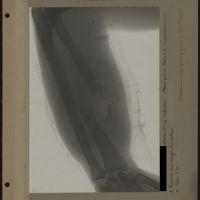

0010 - Page 6 - [Radiographie du bras]0010 - Page 6 - [Radiographie du bras]

0024 - Page 20 - [Radiographie du bras]0024 - Page 20 - [Radiographie du bras]